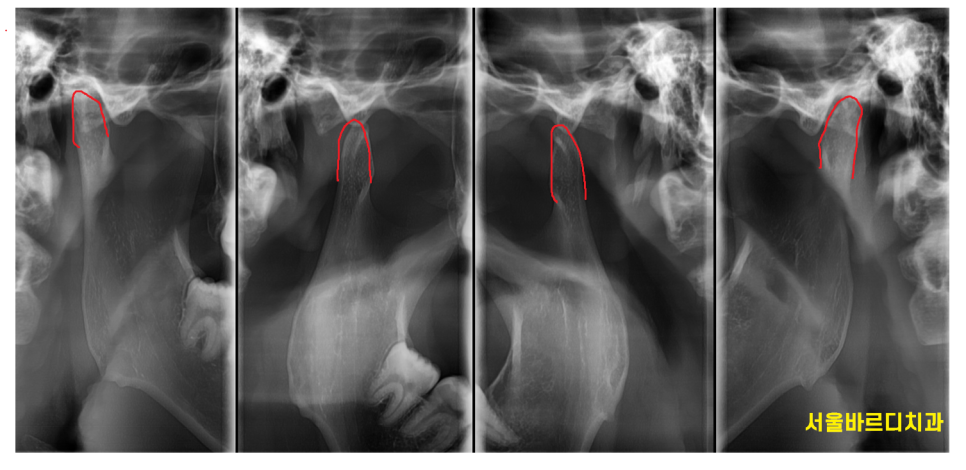

턱관절 x ray 촬영도 치과에서 촬영 가능합니다.240426

정밀한 X-ray 촬영과 문진을 통해 현재 턱관절 상태를 파악하고,

필요한 경우 스플린트 장치나 물리치료 등 맞춤형 치료를 제안해 드립니다.